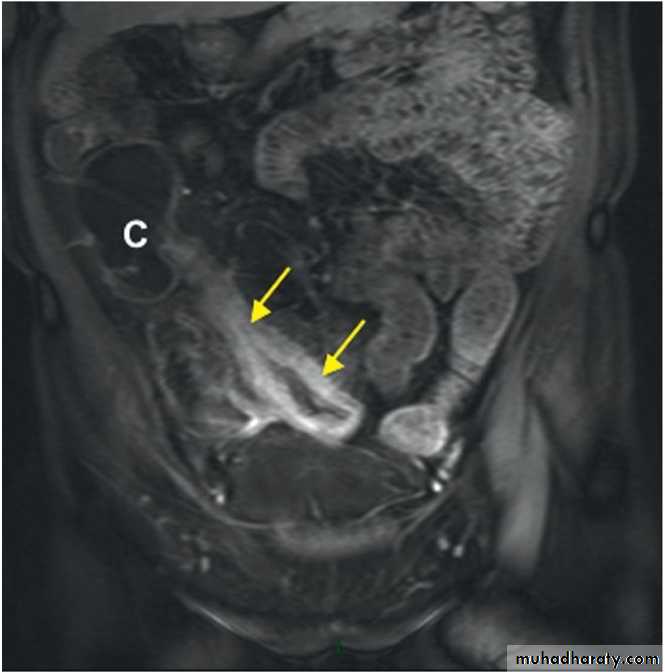

Ileal Crohn's disease. MRI scan showing a thickened, narrowed loop of ileum with enhancement after MR contrast (arrows), consistent with active Crohn's disease. Normal small bowel can be seen at the top right of the image. (C = caecum)